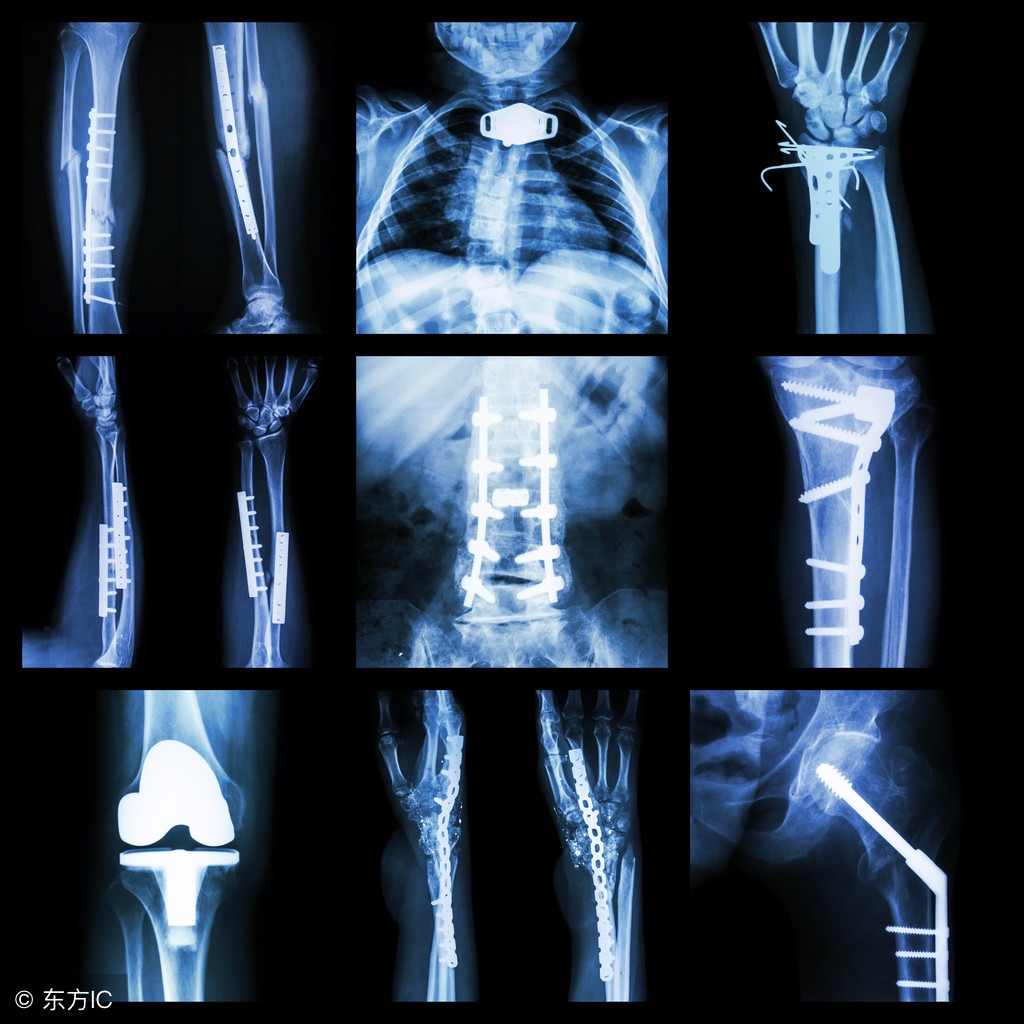

术后拍片是复查工作的一项重要内容,目的是了解骨折复位、固定有没有变化、骨折愈合情况怎么样等等。复查内容不仅限于拍片,还包括对手术部位肿胀程度、关节活动范围、疼痛、出院前残留的症状等改善或加重情况,用以评估患者病情,总结治疗经验,修正康复计划。

术后1个月 患者此时复查内容除上述内容外,需拍X线贯穿骨折复位及钢板(钢钉)位置,如有病情变化及时给予干预。

术后3个月 患者继续复查上述项目,再次复查X线,评估骨折端复位、内固定无位置情况,观察有无骨痂形成,位下肢骨折负重提供客观依据。

术后6个月 复查X线,正常情况下可见明显骨痂形成,下次复查可推迟到1年,若骨痂形成不满意,以后每3个月复查1次,直至骨折愈合,若出现骨折不愈合及时再次手术干预。